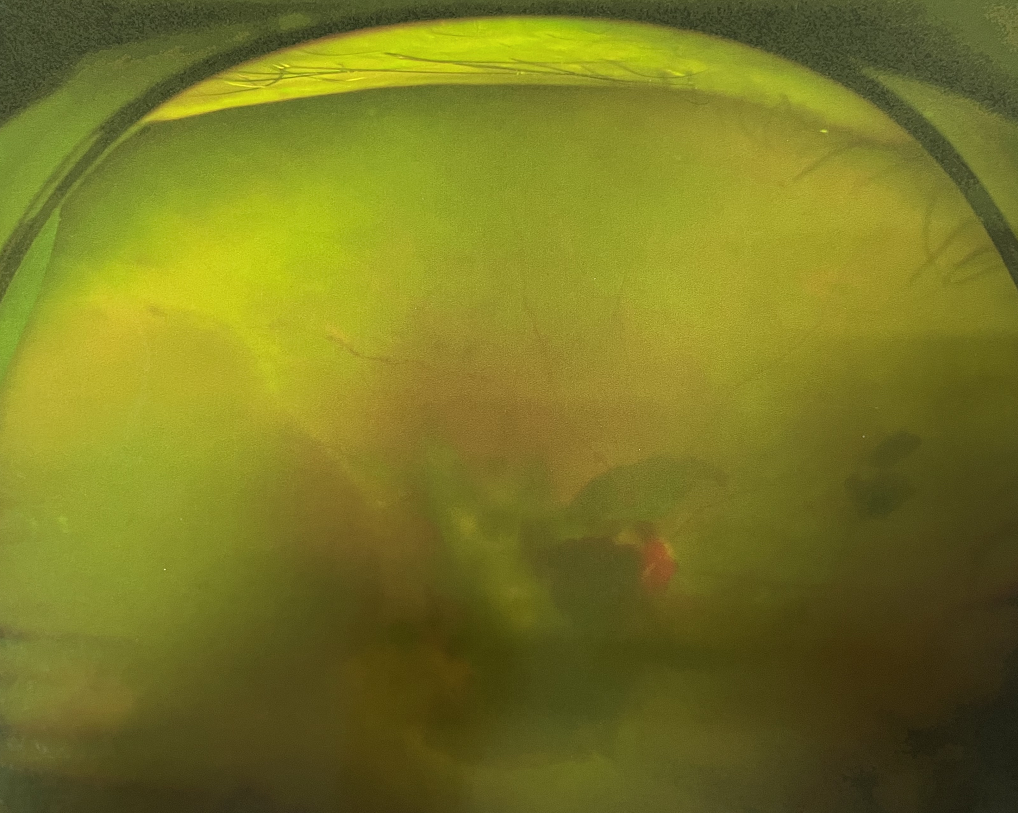

右眼術(shù)前

四十多歲的王女士,患高血壓病及Ⅱ型糖尿病多年,一直靠藥物控制血壓和血糖。去年,王女士右眼看手機(jī)時感覺視物不清,總感覺眼前有一層霧,視力也逐漸下降,于是來廈門大學(xué)附屬廈門眼科中心就診。

眼底病專科張小虎醫(yī)生檢查后,診斷王女士為“雙眼玻璃體積血、雙眼糖尿病視網(wǎng)膜病變V期”。(V期即5期,纖維增生期,出現(xiàn)纖維膜,可伴視網(wǎng)膜前出血或玻璃體出血。)

張小虎醫(yī)生為王女士進(jìn)行右眼玻璃體腔注藥術(shù),3天后進(jìn)行右眼23G玻璃體切割術(shù)后視力有所提升。

4個月后王女士來院取硅油,取油后視力恢復(fù)到0.6。“當(dāng)時來的時候真的只能看到模糊的影子,特別害怕覺得完了,想說眼睛估計要瞎了,沒想到手術(shù)后視力竟然提升了,現(xiàn)在也看得比較清楚了。”王女士說到。

張小虎醫(yī)生表示,糖網(wǎng)病進(jìn)展到嚴(yán)重增殖期帶來的視力損傷往往是極其嚴(yán)重的,目前王女士右眼從術(shù)前0.02恢復(fù)到術(shù)后0.6,已屬十分難得。